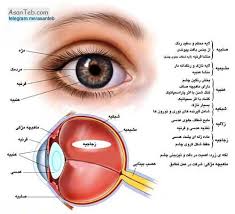

قیمت: 78٬750 تومان - دسته بندی فایل: پاورپوینتپاورپوینت جامع و کامل ساختمان چشم انسان

پاورپوینت جامع و کامل ساختمان چشم انسان